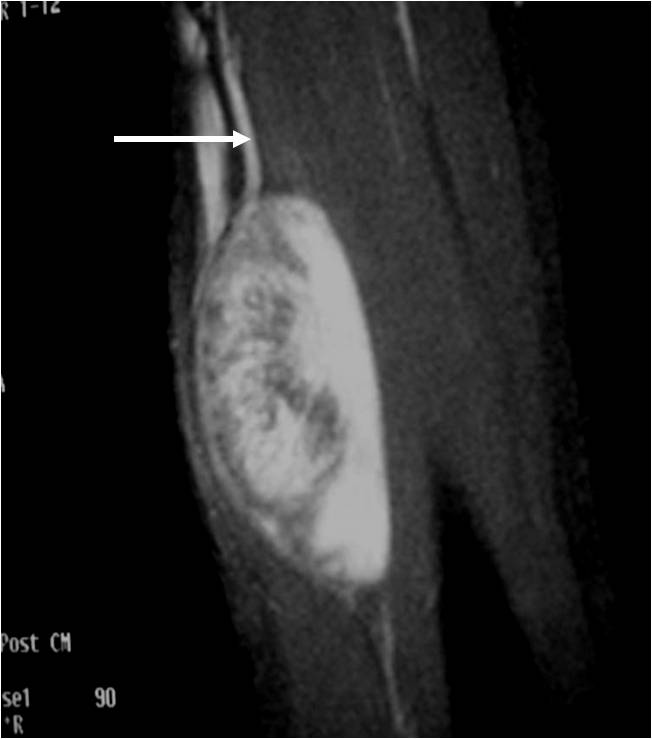

MRI appearance (Fig. 1 – 4)

• Nerve: Tubular structure visualized entering and exiting the mass (may be difficult to see with small lesions or lesions of the trunk or retroperitoneum) (Fig. 2 & 4)

o Target Sign: Low signal central area (cellular/collagenous area; Antoni A) and high signal peripheral area (myxoid area; Antoni B)

Fig. 1-4 MR image demonstrates a 5 cm intermuscular mass in the anterior compartment of the arm arising along the course of the neurovascular structures. Isointense to muscle on T1W image and heterogeneous high signal on T2W with low signal in the central area (Antoni A) and peripheral high signal (Antoni B), known as “Target Sign”. Coronal image shows a structure entering and exiting the mass (median nerve).